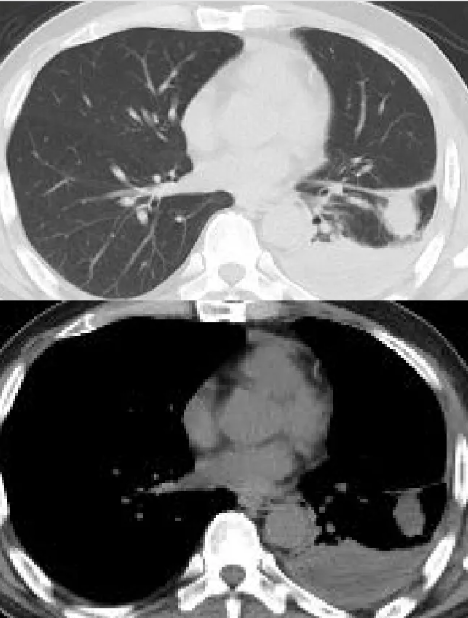

2025-12-20 出现寒战、发热,Tmax 39.6℃,伴咳嗽、咳黄脓痰,痰恶臭味。12-24于我院发热门诊查血常规WBC 6.32×10^9/L,N 72.6%;CRP 35.6mg/L,PCT 0.36ng/mL;D-二聚体 4.69mg/L。胸部CT: 左下肺渗出、部分不张,较2025-12-15片稍好转,左侧胸腔积液(部分包裹)较前稍减少,纵隔多发稍大淋巴结(较前增大)。诉口服莫西沙星后腹泻呕吐明显,予美罗培南抗感染,体温高峰下降,仍有咳嗽咳黄脓痰。2025-12-29尝试B超下胸腔穿刺引流失败。2025-12-29为明确肺内病灶病因并诊治收入中山医院感染病科。